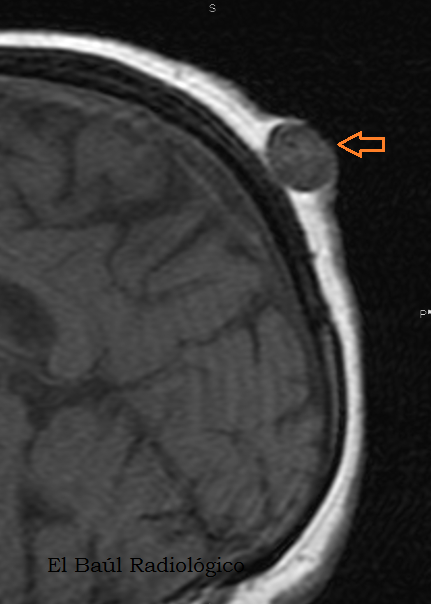

FIGURA 6) Los quistes sebáceos tambien se detectan en las exploraciones de TRM. Se presentan como un nódulo hipodenso, bien delimitado, que no tiene relación con el cráneo.

(Sebaceous cystsare detectedalsoin the explorations ofMRI.They appear ashypodense, well-defined nodes, which has no relation to the skull).

FIGURA 4) En esta imagen se puede apreciar la cápsula del quiste. No siempre es visible.

(In this imagecan be seenthe cyst capsule. It is not alwaysvisible)